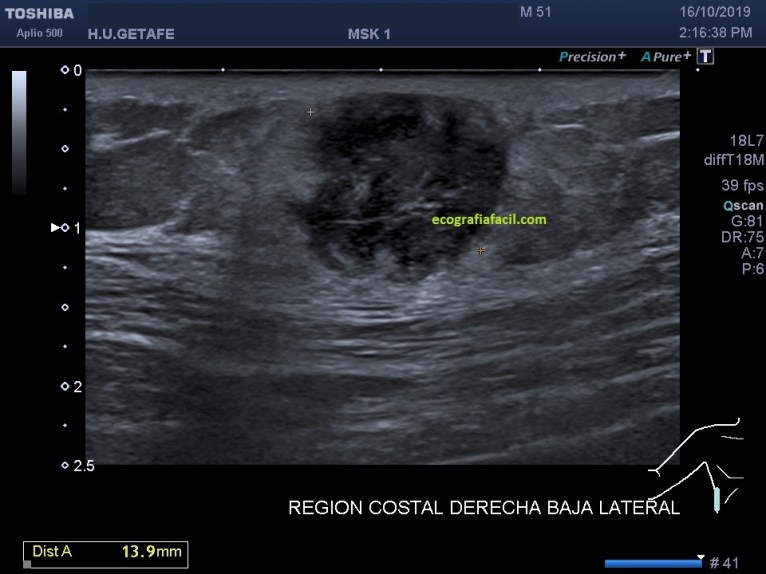

En la imagen 1 y 2, las medidas, básico en cualquier estudio de una lesión. La imagen 3 nos muestra la vascularización de la lesión, que lo está, aunque no es una vascularización exacerbada.

La LOE (lesión ocupante de espacio) es hipoecogénica, heterogénea, sólida, con bordes definidos, pero agrestes, aunque respeta tanto la piel como la fascia.